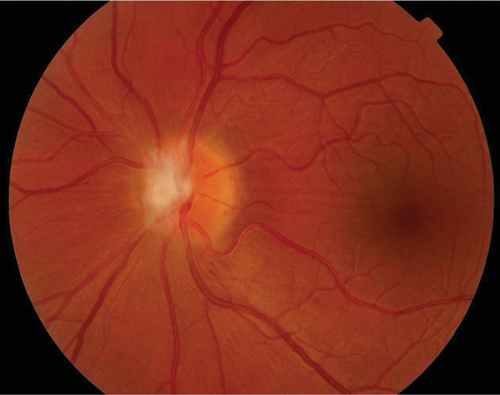

Case 3

A 69-year-old Caucasian lady presented with painful, sequential, bilateral visual loss over six weeks. Vision was 6/60 on the right and CF left eye. Initially, the optic nerves were not swollen. There was a history of AChR antibody-positive myasthenia gravis. MRI showed high signal in both optic nerves and AQP4 ab was positive in the serum. She improved partially after high dose intravenous steroid for five days and is currently on long-term immunosuppression. This is an atypical optic neuritis where the key diagnostic features are bilateral, severe loss of vision over several weeks. The diagnosis of neuromyelitis optica is difficult to diagnose if it presents solely in the optic nerves and especially in the elderly. A past history of autoimmunity (myasthenia gravis) was critical in directing the investigation.

Figure 2: Case 3 - right (top) and left (bottom) optic nerves.